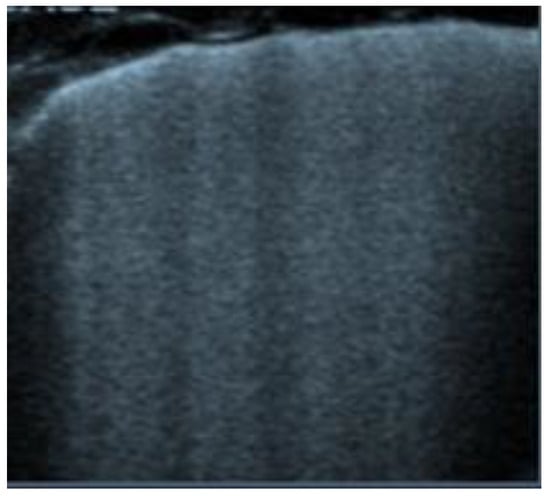

Figure 5. Lung ultrasonography, signs in motion mode (M-mode): seashore sign, indicative of the physiological sliding of the pleural line.